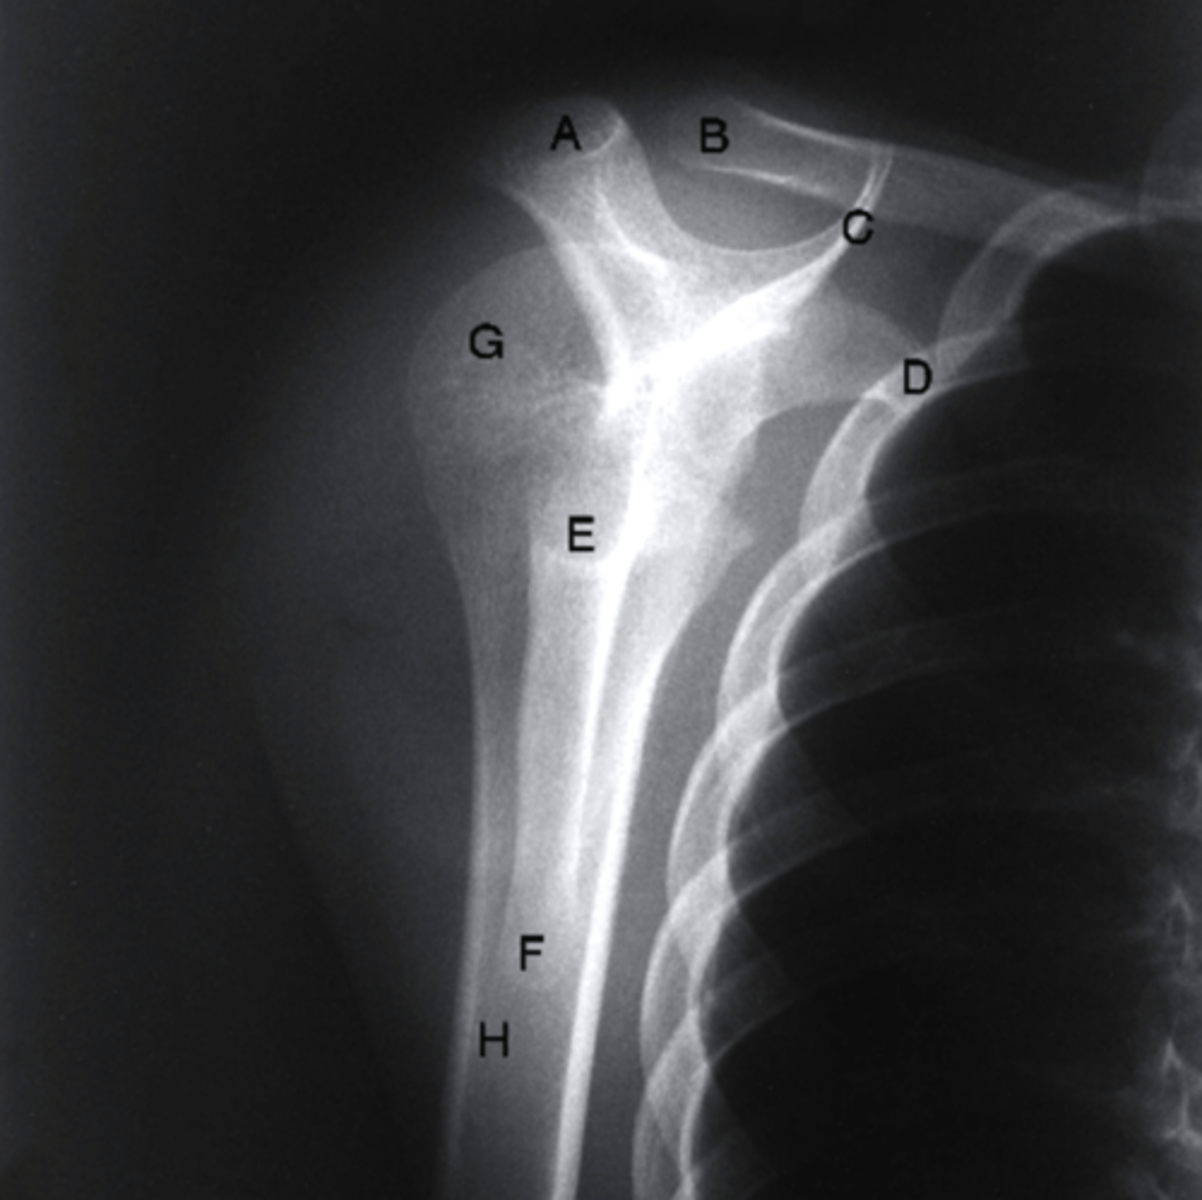

Which structure is labeled letter "D" in the image?

coracoid process